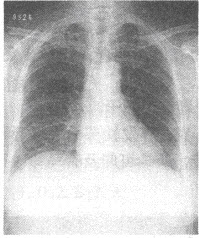

患者,女,65岁。左侧肢体偏瘫,言语不清2天入院,曾有高血压病史多年。影像学检查如下图。

(单选题)对该病最具有早期诊断价值的影像学检查方法是()

A:头颅CT

B:头颅X线平片

C:磁共振DWI序列

D:DSA检查

E:超声

F:以上都不是